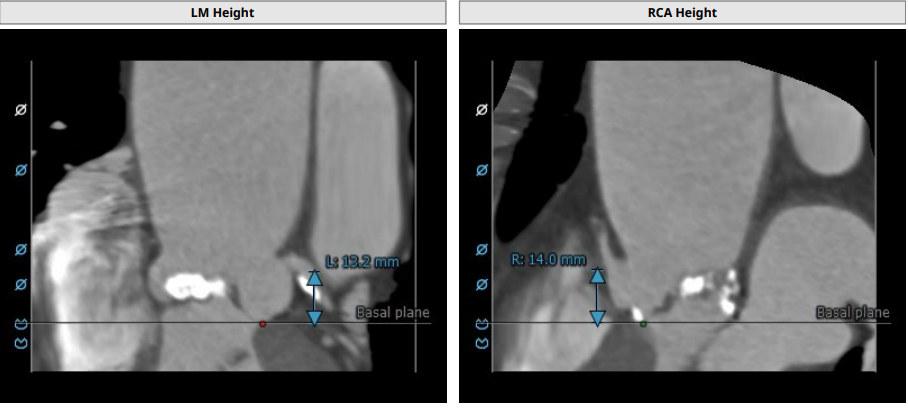

LCA:13.2 mm,RCC:14.0 mm

左右冠高度合适

TYPE1 型二叶瓣,重度钙化,钙化呈单边分布,主要集中在无冠窦侧,左右可见非钙化脊,左冠高度约 13.2 mm,右冠高度约 14 mm,法式窦结构大,STJ 高度约 19.4 mm、直径约 30.8 mm,升主动脉可见增宽,最宽处约 47.1 mm,心脏角度约 46°,左室大小可,右窦居中体位:RAO4°、CAU21°,左冠切线位:LAO2°、CAU16°。